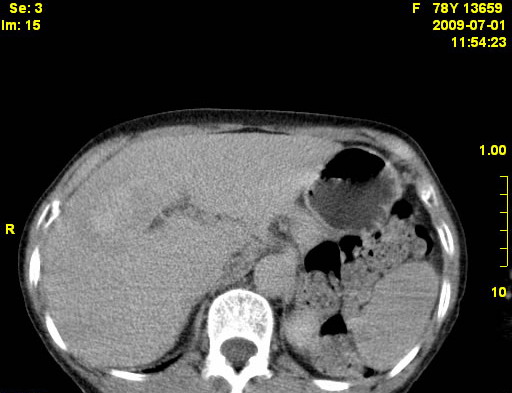

以下是引用zjzjr在2009-7-3 11:02:00的发言:[br]动脉期不均匀强化,门脉期及延迟期强化明显,肝门部见肿大淋巴结影,肝内胆管扩张.考虑肝右叶前段胆管细胞癌伴肝门淋巴结转移,胆内胆管扩张.慢性胆囊炎.

以下是引用dsl555在2009-7-4 10:59:00的发言:[br]考虑肝右叶前段胆管细胞癌伴肝门淋巴结转移,胆内胆管扩张.慢性胆囊炎. [br][br]支持。